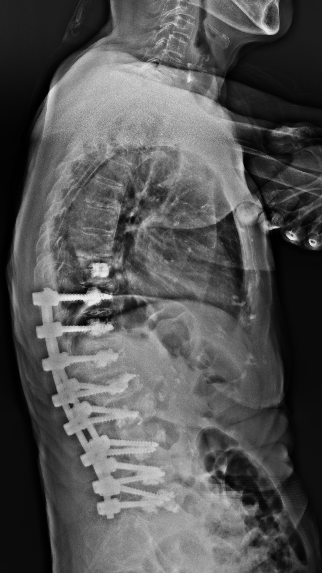

术前(左)和术后(右)对比: 术后脊柱后凸矫正,骨折椎体强化固定

手术过程顺利,术后快速康复,实现早期活动

彭旻副主任团队为吴婆婆成功实施了 “后路脊柱后凸截骨矫形、骨水泥钉内固定、后外侧融合术”。术后,在加速康复理念的指导下,吴婆婆恢复顺利,腰背部疼痛显著缓解,术后第二天即可在支具保护下坐起,并逐步开始下地站立行走,避免了长期卧床带来的并发症。